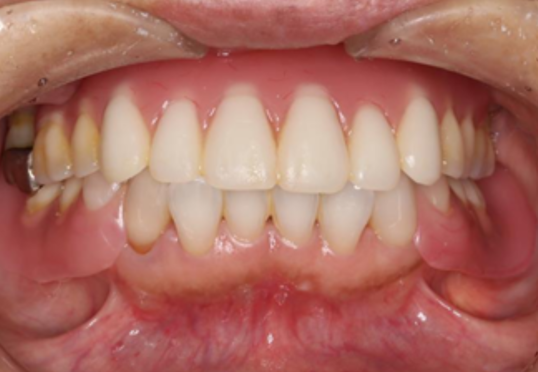

症例